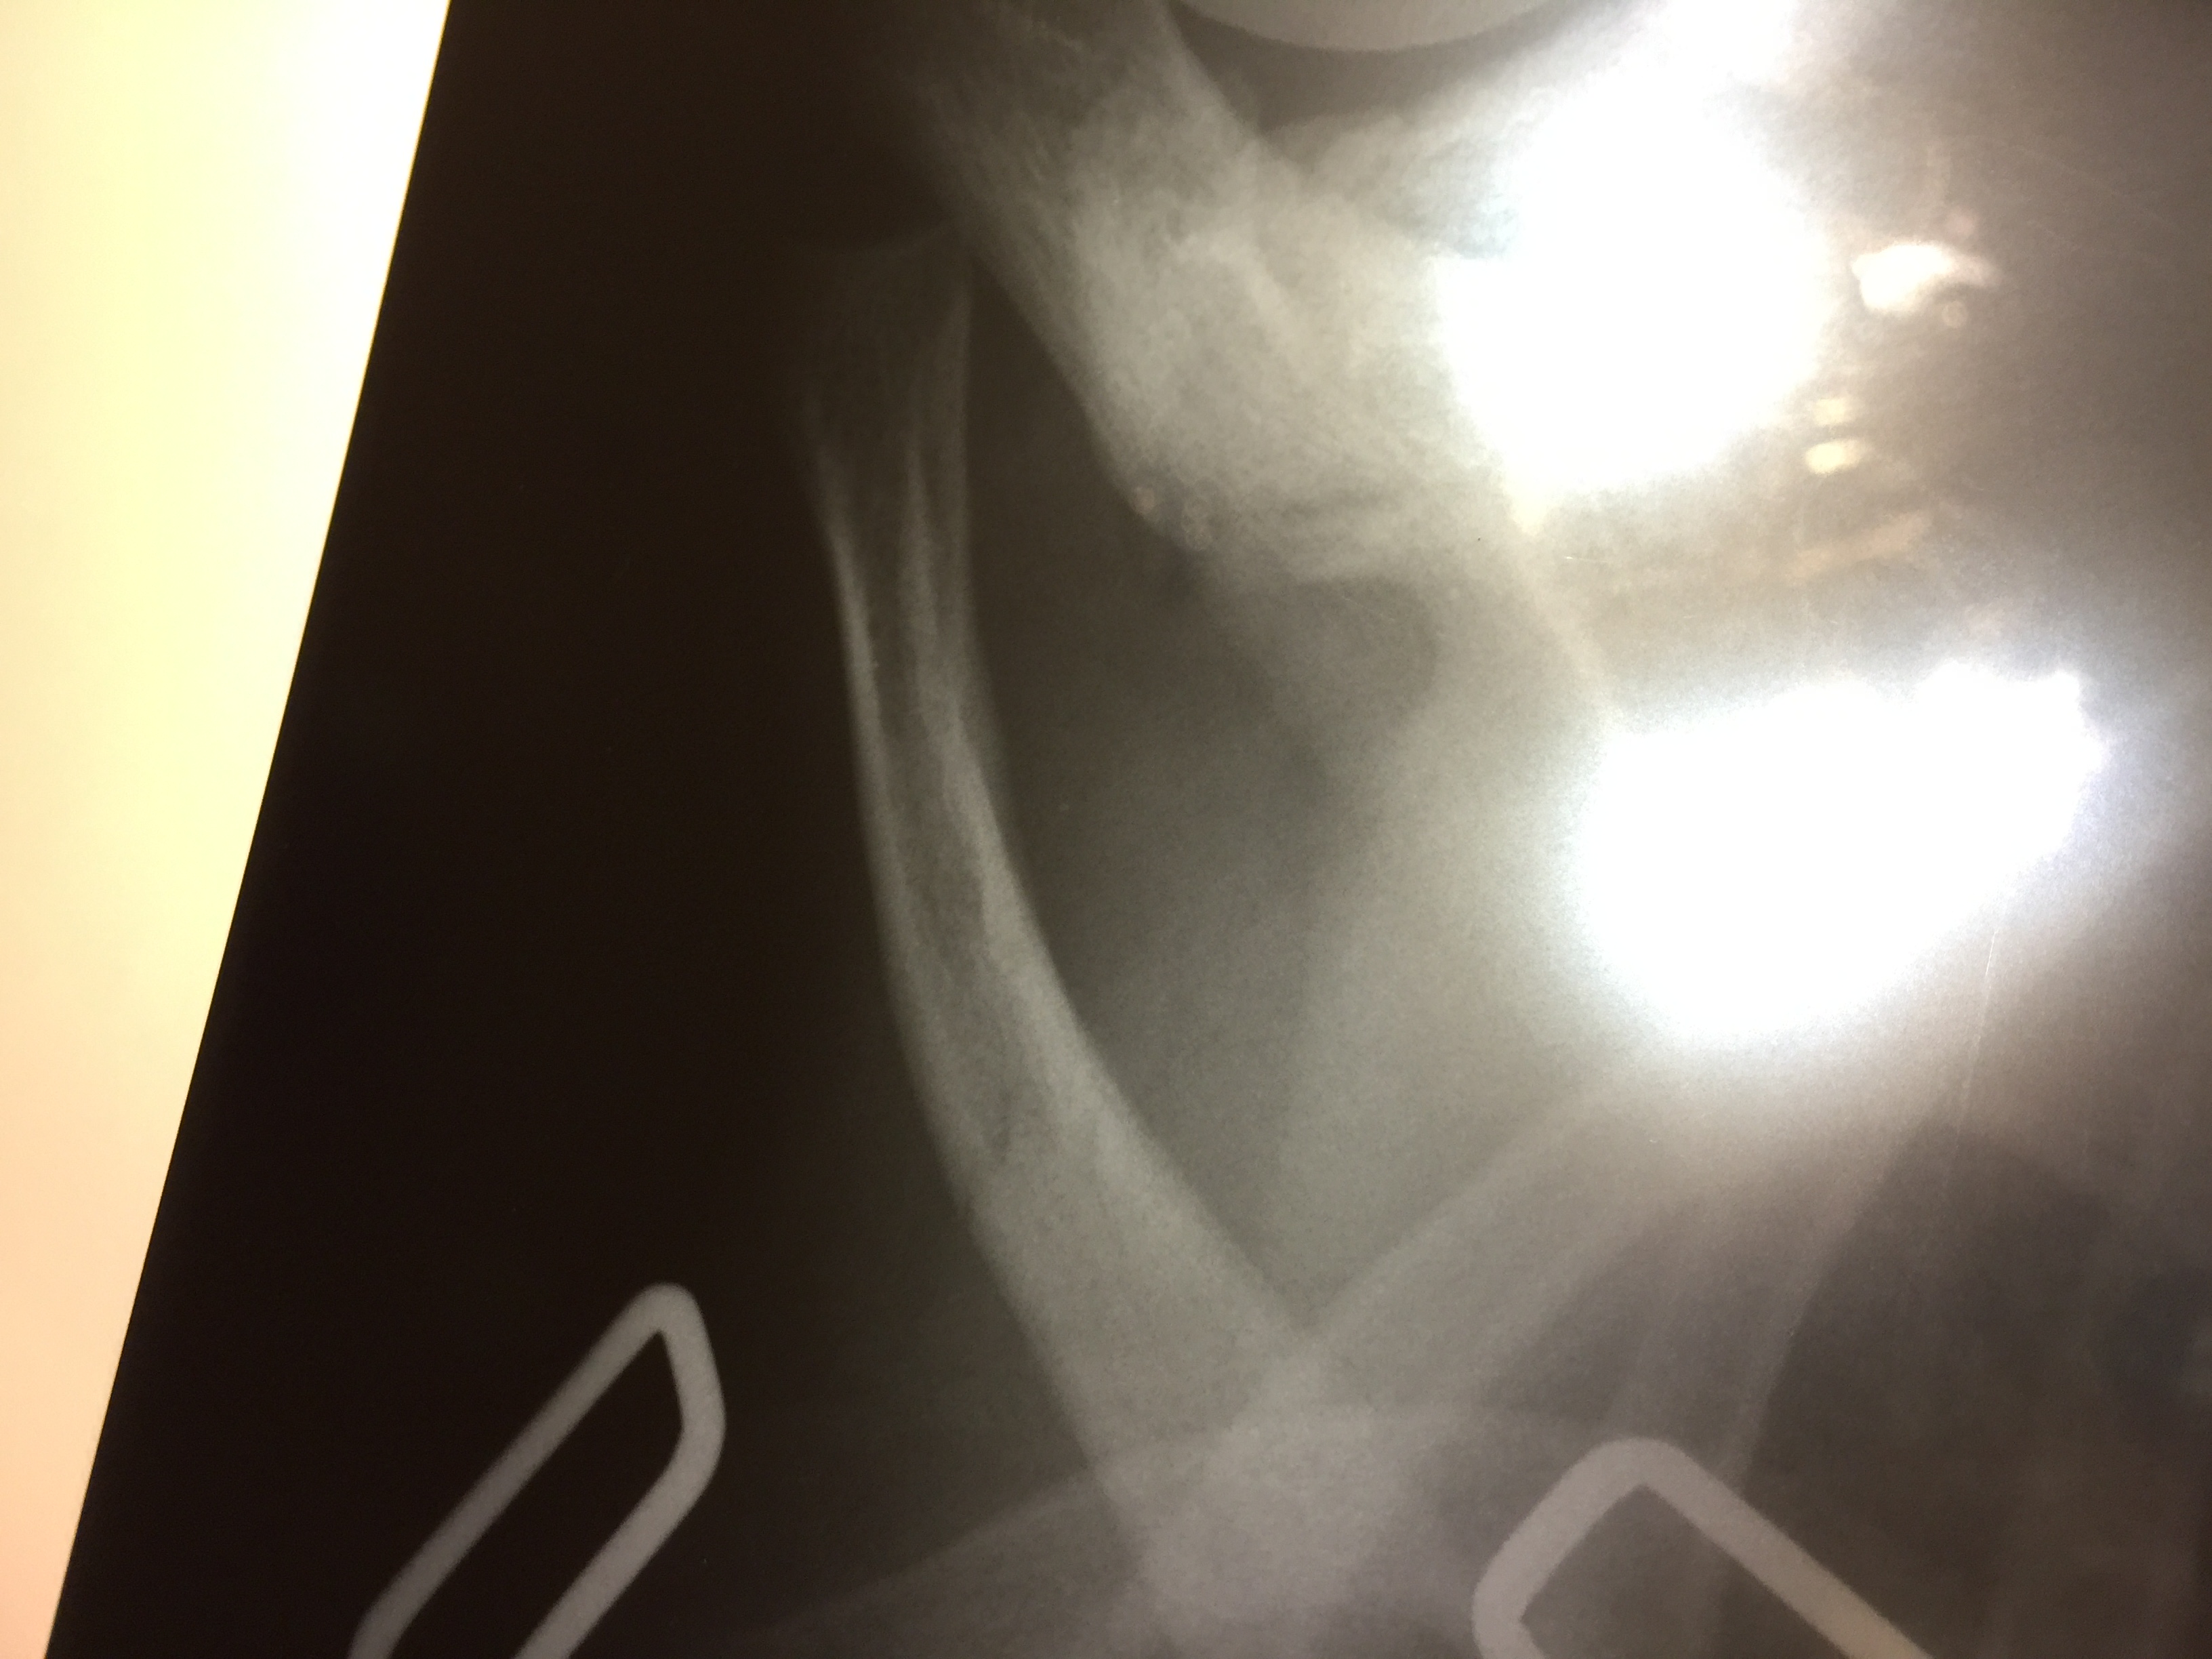

В больничку на Алишера не поехали, так как до сих пор от весенних впечатлений от их условий отойти не можем. Пока катился по нашим тянучкам до клуба, друзья созвонились с ОхМатДетом, и нас там уже ждали. Вердикт - перелом ключицы... Пока обошлись наложением колец, в Пн на контрольный снимок поедем, надеюсь, что все без операции обойдется.

image.jpeg (1.7 MiB) Просмотров: 5631